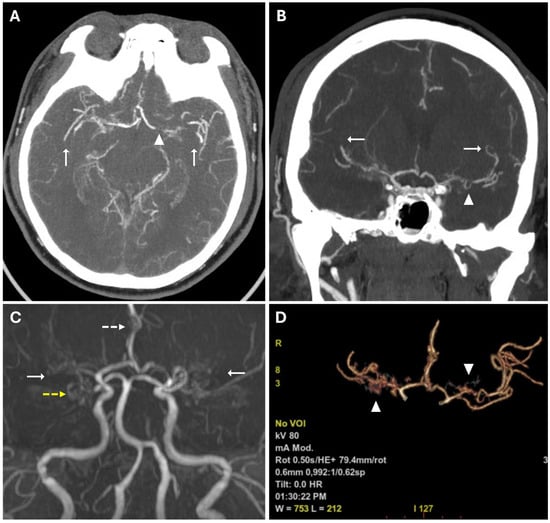

These findings suggested acute ischemic lesions in the right middle cerebral artery territory. There were no hemorrhagic lesions or mass effect on the encephalic parenchyma. Computed tomography angiography (CTA) examination showed reduced caliber and parietal irregularity of M1–M2 tracts of the middle cerebral artery bilaterally, with steno-occlusive tract-like changes. Additionally, vascular ectasia of deep lenticular arteries and the right anterior cerebral artery were also detected (Figure 2).

Figure 2. (A,B) CTA images in axial (A) and coronal (B) views, using a Maximum Intensity Projection (MIP) reconstruction, show reduced caliber and parietal irregularity of the M1-M2 tract bilaterally (white arrows) with severe stenotic tract in the left MCA (white arrowheads). (C) 3d MRA sequence shows multiple steno-occlusive changes in M1-M2 bilaterally (white arrows), irregular caliber of the right ACA (white dotted arrows), and right PCA (yellow dotted arrows). (D) Volume rendering reconstruction of CTA shows abnormal collateral perforators (white arrowheads).

MRA confirmed the reduced caliber and wall irregularities with steno-occlusive changes in M1–M2 tracts of the middle cerebral artery bilaterally, predominantly on the right. The A2 segment of the right anterior cerebral artery (ACA) and the P2 segment of the right posterior cerebral artery (PCA) also showed irregular caliber due to alternations of stenotic and dilated tracts (Figure 2).